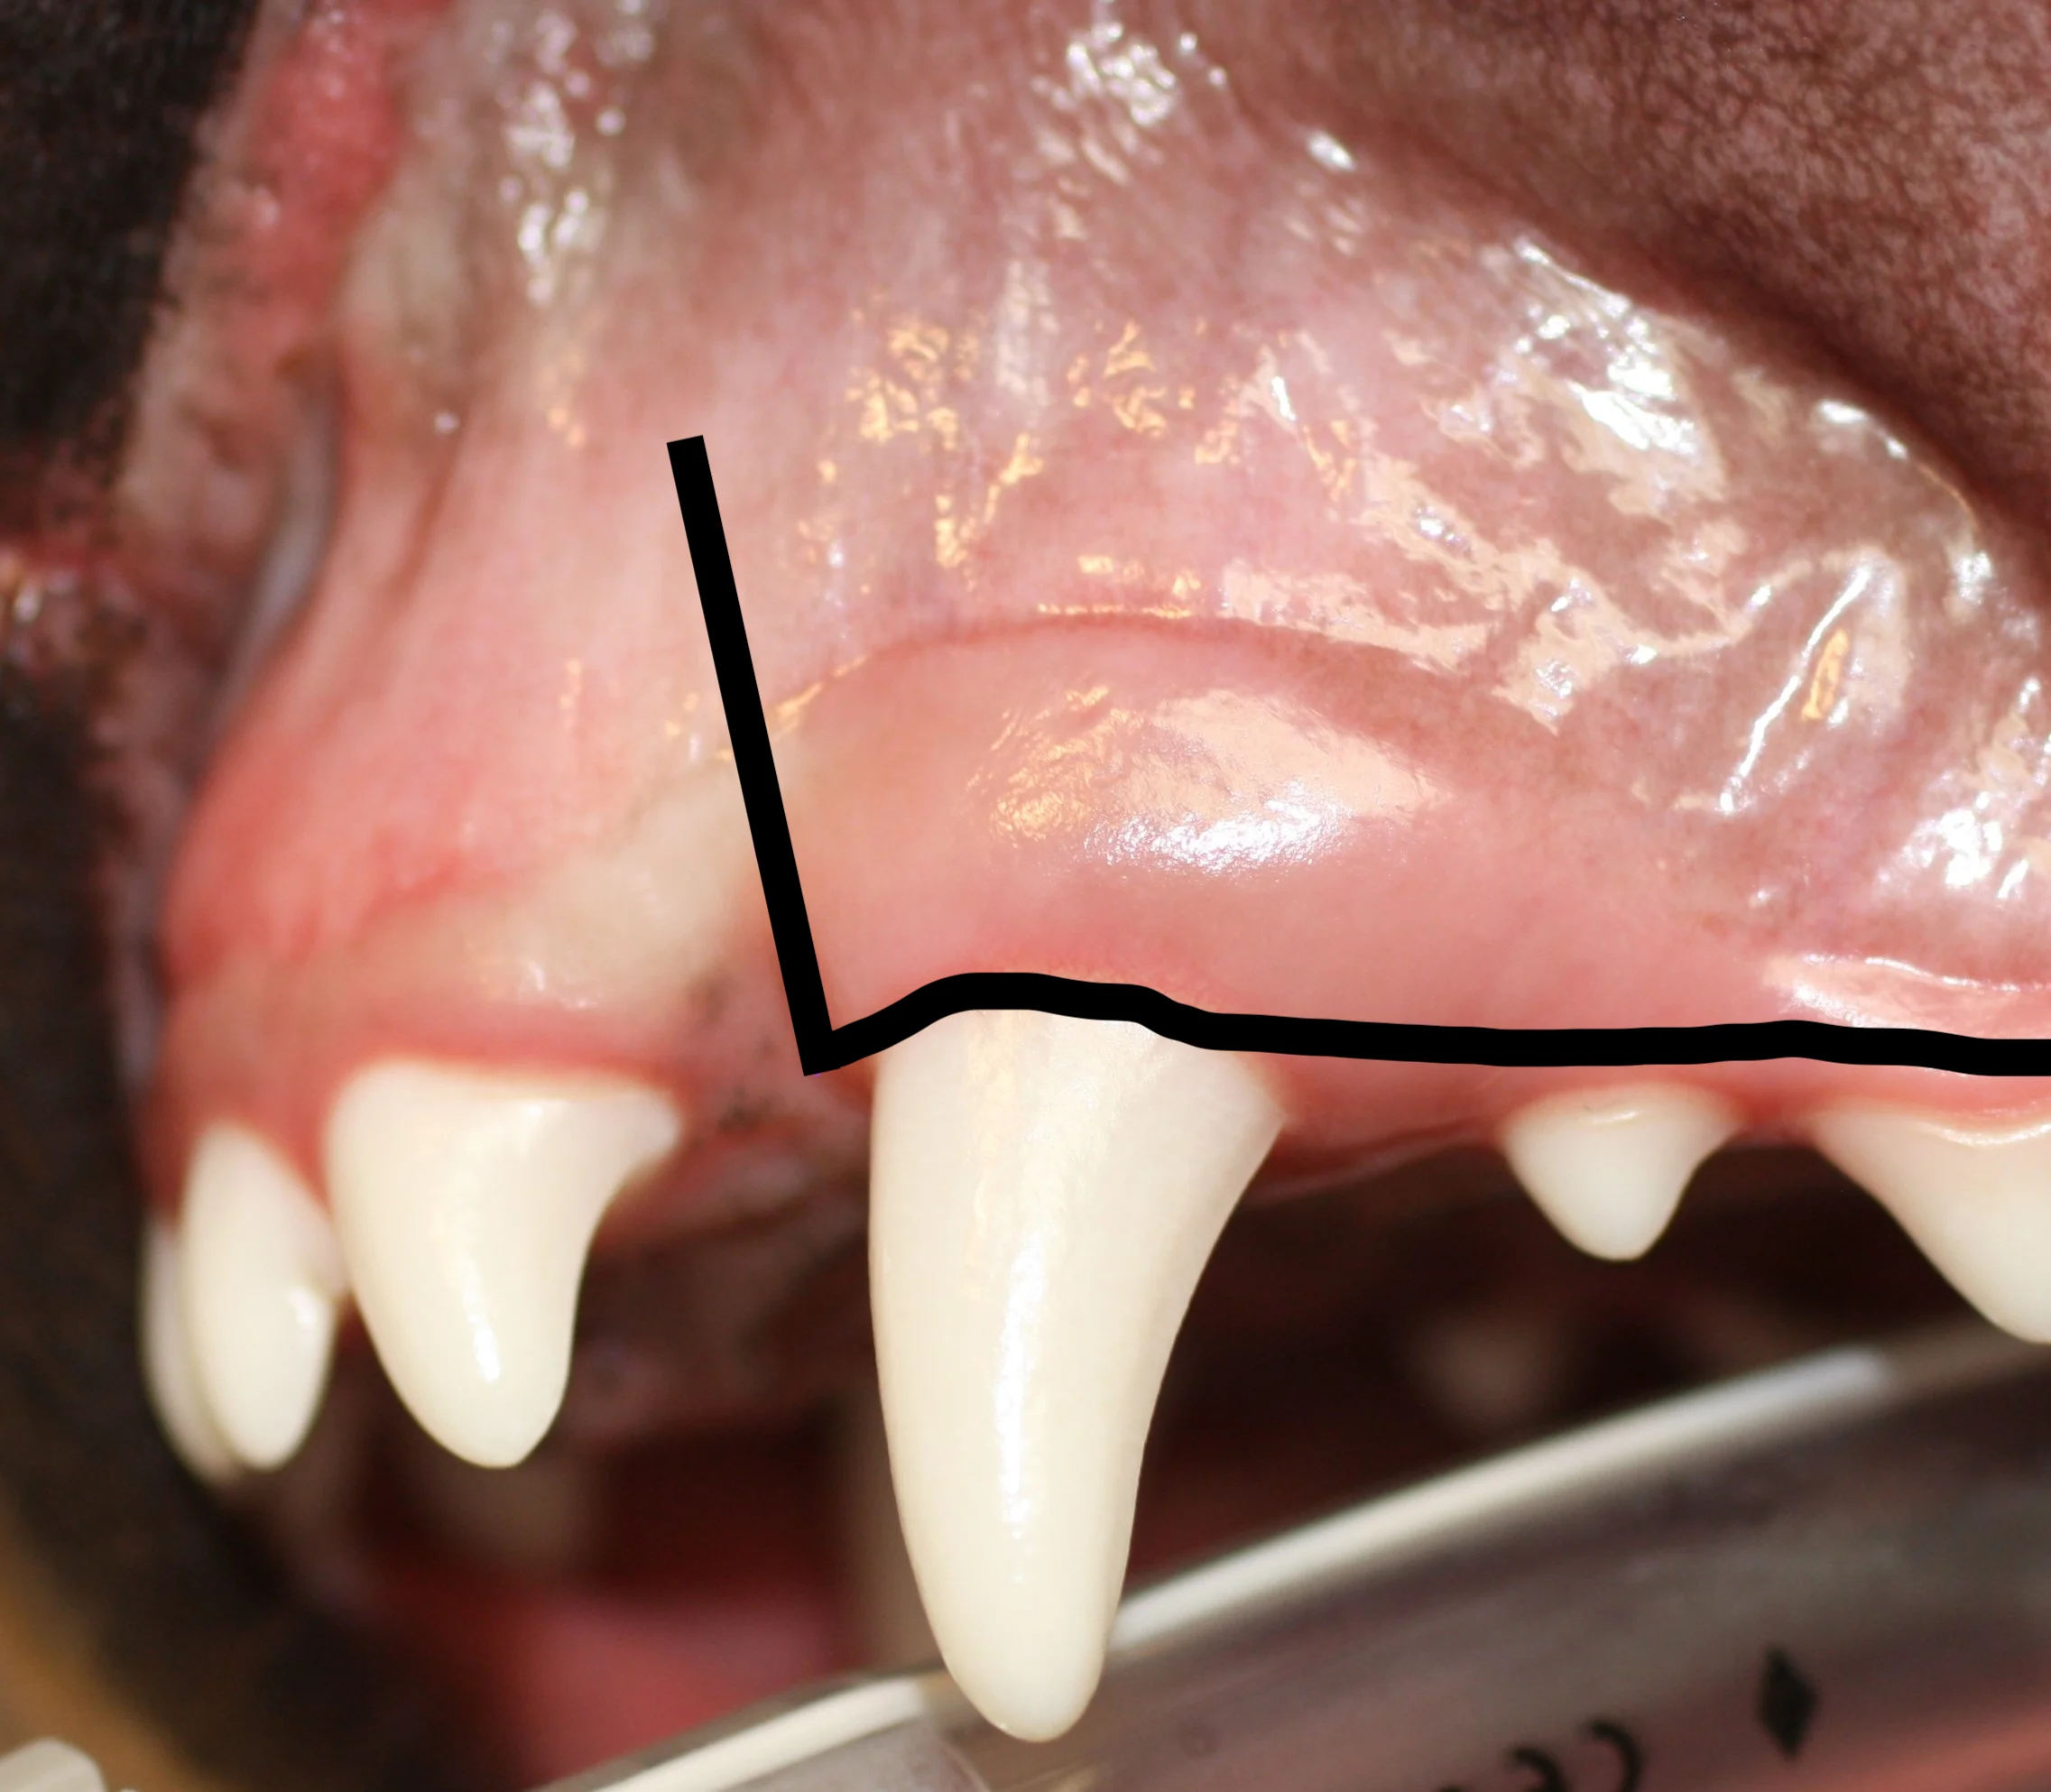

Triangular Flap

A triangular flap is created by making a mesial releasing incision and an incision at the ventral alveolar border (line). The releasing incision should extend at least to the level of the widest part of the root.

Envelope Flap

An envelope flap is created by making an incision at the ventral alveolar border (line). This type of flap may be preferred because vertical releasing incisions can contribute to complications (eg, dehiscence).